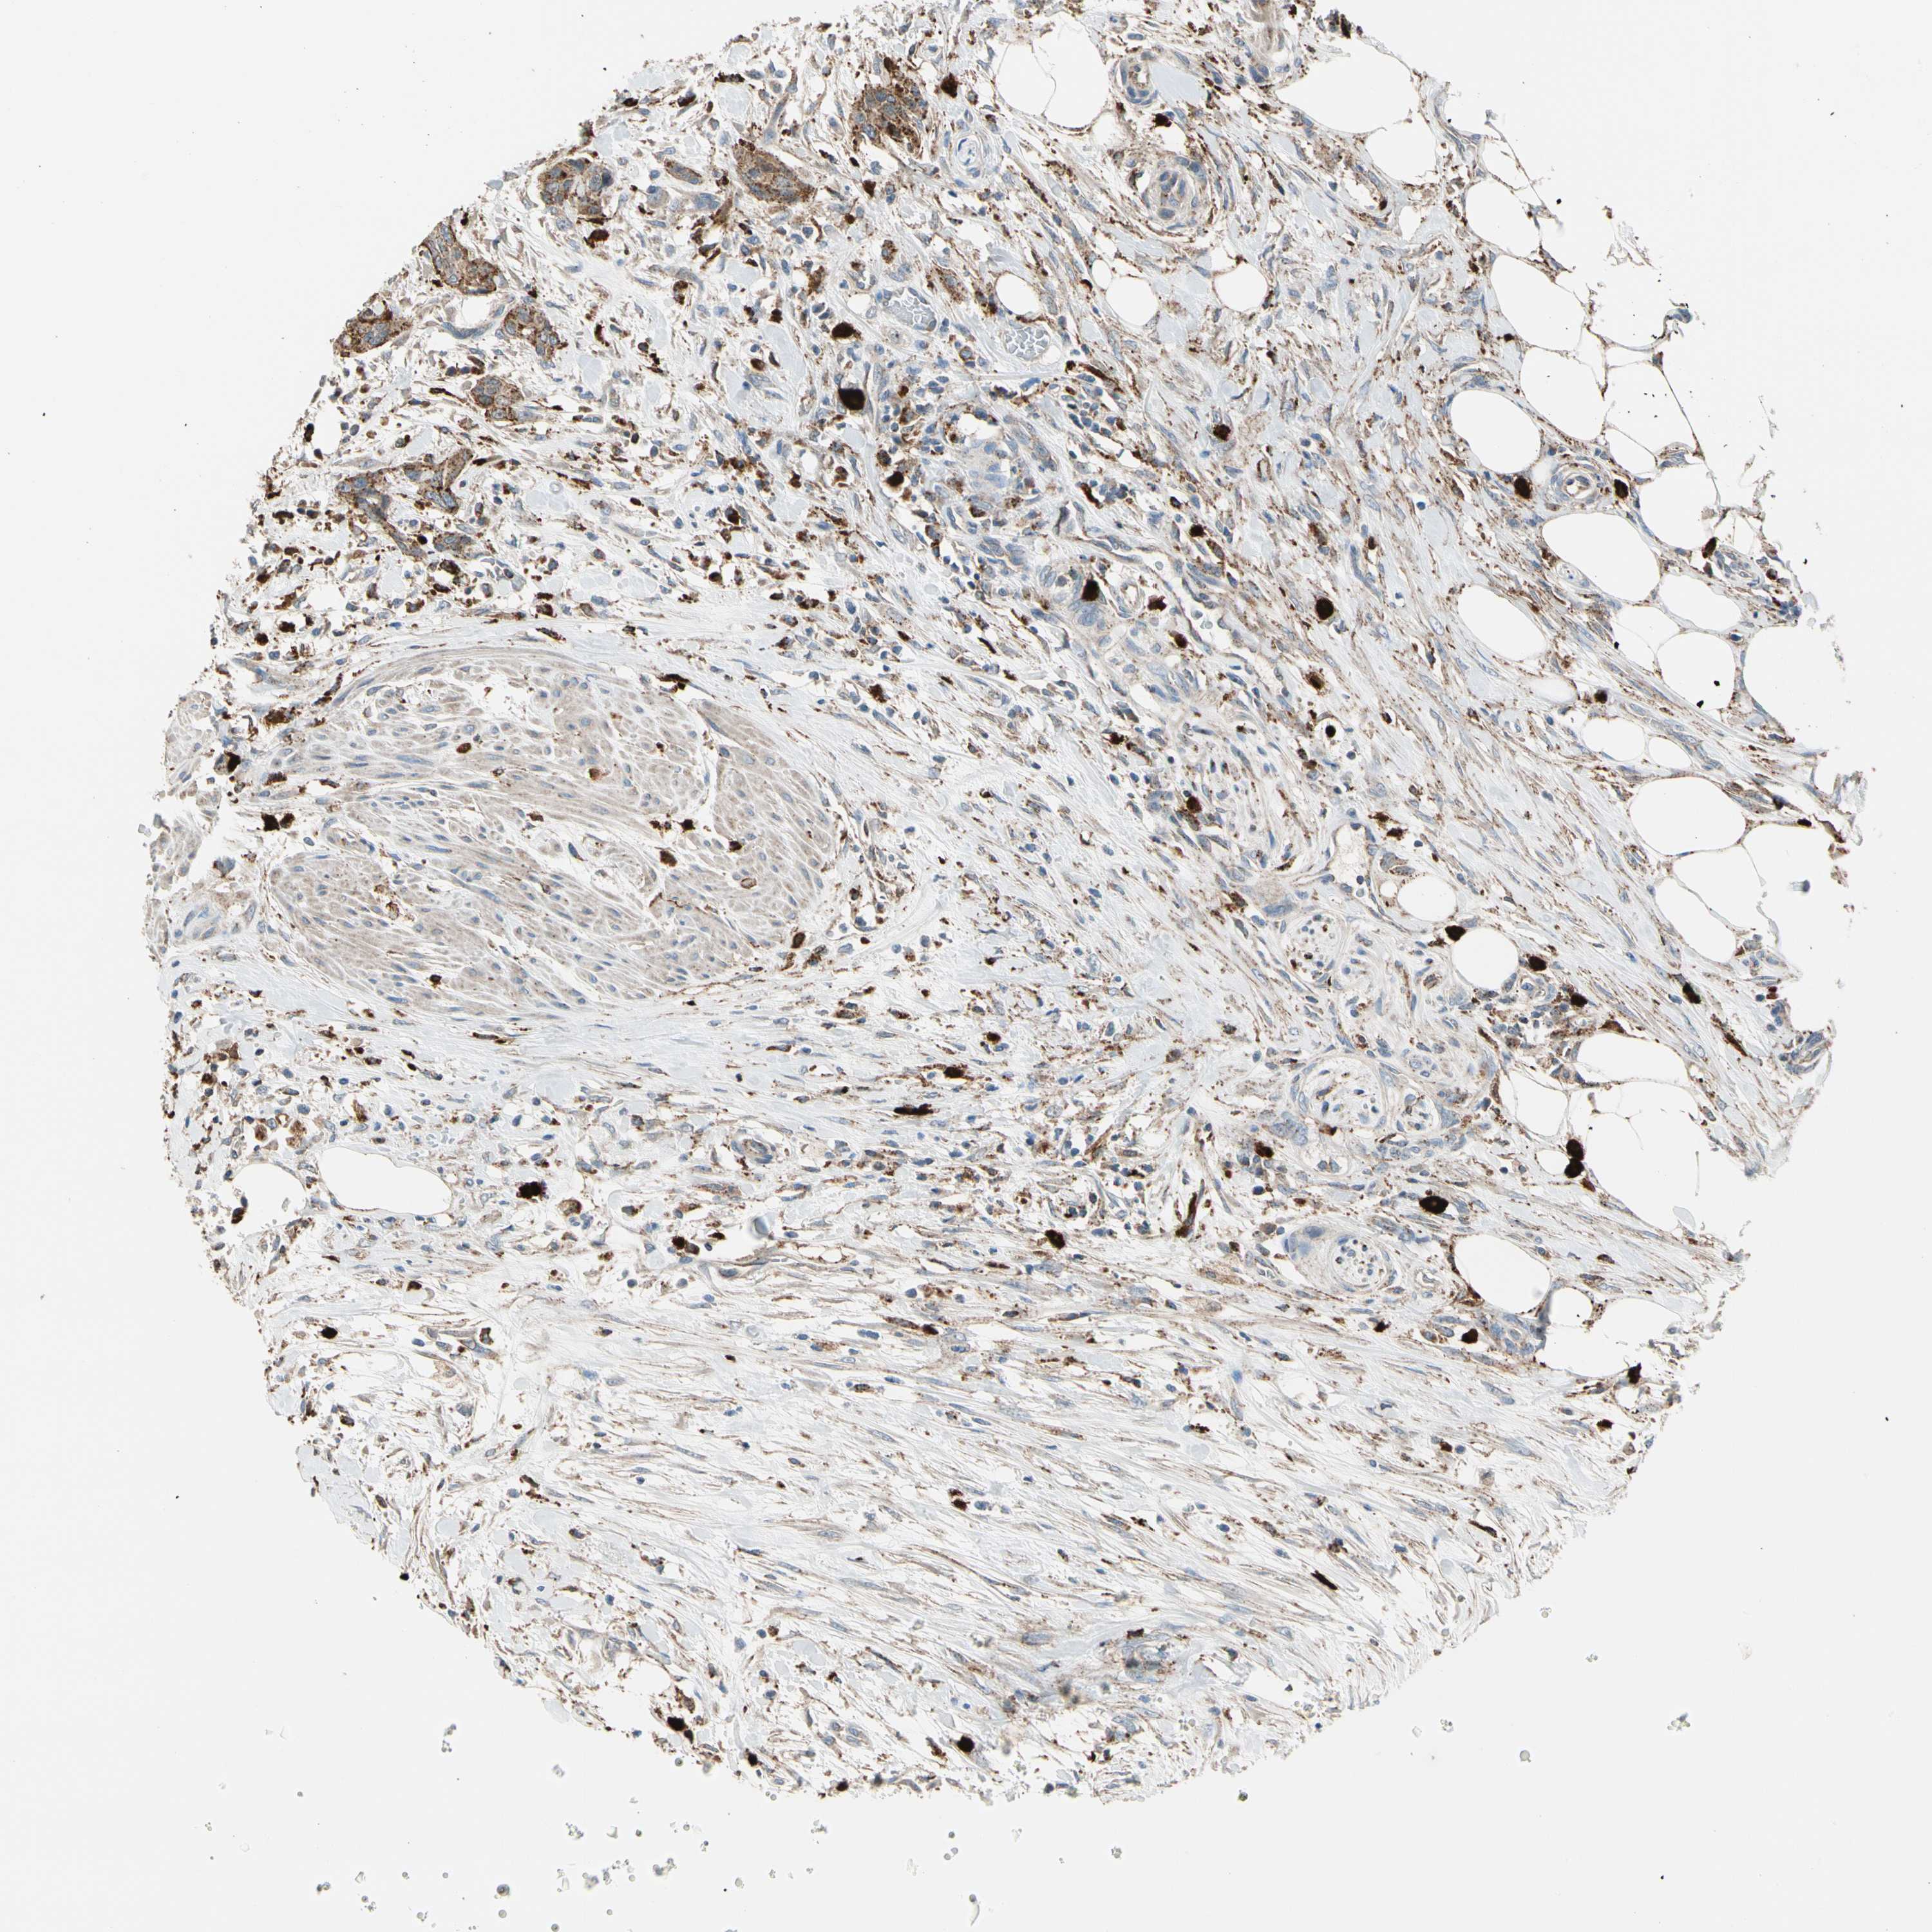

UROTHELIAL CANCER - Protein expressioni

A mouse-over function shows sample information and annotation data. Click on an image to view it in a full screen mode. Samples can be filtered based on level of antibody staining by selecting one or several of the following categories: high, medium, low and not detected. The assay and annotation is described here.

Note that samples used for immunohistochemistry by the Human Protein Atlas do not correspond to samples in the TCGA dataset.

Antibody stainingi

Antibody staining in the annotated cell types in the current human tissue is reported as not detected, low, medium, or high, based on conventional immunohistochemistry profiling in selected tissues. This score is based on the combination of the staining intensity and fraction of stained cells.

Each image is clickable and will lead to virtual microscopy that enables deeper exploration of all samples and also displays staining intensity scores, fraction scores and subcellular localization as well as patient and tissue information for each sample.

Antibody HPA008063

Staining

High

Medium

Low

Not detected

Intensity

Strong

Moderate

Weak

Negative

Quantity

>75%

75%-25%

<25%

None

Location

Nuclear

Cytoplasmic/membranous

Cytoplasmic/membranous,nuclear

Urothelial carcinoma, Low grade

Urothelial carcinoma, High grade